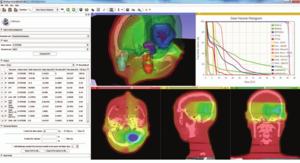

Treatment Planning and Delivery of Whole Brain Irradiation with Hippocampal Avoidance in Rats

Publication: PLoS One. 2015 Dec 4;10(12):e0143208. PMID: 26636762 | PDF Authors: Cramer CK, Yoon SW, Reinsvold M, Joo KM, Norris H, Hood RC, Adamson JD, Klein RC, Kirsch DG, Oldham M. Institution: Department of Radiation Oncology, Duke University Medical Center, Durham, NC, USA. Background/Purpose: Despite the clinical benefit of whole brain radiotherapy (WBRT), patients and physicians are concerned by the long-term impact on cognitive functioning. Many studies investigating the molecular and cellular impact of WBRT have used rodent models. However, there has not been a rodent protocol comparable to the recently reported Radiation Therapy Oncology Group (RTOG) protocol for WBRT with hippocampal avoidance (HA) which is intended to spare cognitive function. The aim of this study was to develop a hippocampal-sparing WBRT protocol in Wistar rats. Methods: The technical and clinical challenges encountered in hippocampal sparing during rat WBRT are substantial. Three key challenges were identified: hippocampal localization, treatment planning, and treatment localization. Hippocampal localization was achieved with sophisticated imaging techniques requiring deformable registration of a rat MRI atlas with a high resolution MRI followed by fusion via rigid registration to a CBCT. Treatment planning employed a Monte Carlo dose calculation in SmART-Plan and creation of 0.5 cm thick lead blocks custom-shaped to match DRR projections. Treatment localization necessitated the on-board image-guidance capability of the XRAD C225Cx micro-CT/micro-irradiator (Precision X-Ray). Treatment was accomplished with opposed lateral fields with 225 KVp X-rays at a current of 13mA filtered through 0.3 mm of copper using a 40x40 mm square collimator and the lead blocks. A single fraction of 4Gy was delivered (2Gy per lateral field) with a 41 second beam on time per field at a dose rate of 304.5 cGy/min. Dosimetric verification of hippocampal sparing was performed using radiochromic film. In vivo verification of HA was performed after delivery of a single 4Gy fraction either with or without HA using γ-H2Ax staining of tissue sections from the brain to quantify the amount of DNA damage in rats treated with HA, WBRT, or sham-irradiated (negative controls). Results: The mean dose delivered to radiochromic film beneath the hippocampal block was 0.52Gy compared to 3.93Gy without the block, indicating an 87% reduction in the dose delivered to the hippocampus. This difference was consistent with doses predicted by Monte Carlo dose calculation. The Dose Volume Histogram (DVH) generated via Monte Carlo simulation showed an underdose of the target volume (brain minus hippocampus) with 50% of the target volume receiving 100% of the prescription isodose as a result of the lateral blocking techniques sparing some midline thalamic and subcortical tissue. Staining of brain sections with anti-phospho-Histone H2A.X (reflecting double-strand DNA breaks) demonstrated that this treatment protocol limited radiation dose to the hippocampus in vivo. The mean signal intensity from γ-H2Ax staining in the cortex was not significantly different from the signal intensity in the cortex of rats treated with WBRT (5.40 v. 5.75, P = 0.32). In contrast, the signal intensity in the hippocampus of rats treated with HA was significantly lower than rats treated with WBRT (4.55 v. 6.93, P = 0.012). Conclusion: Despite the challenges of planning conformal treatments for small volumes in rodents, our dosimetric and in vivo data show that WBRT with HA is feasible in rats. This study provides a useful platform for further application and refinement of the technique. Funding:

MRI with labeled structures from atlas registered to the CBCT. Registration was carried out with the open source imaging tool 3D Slicer, Version 4.4.0. |